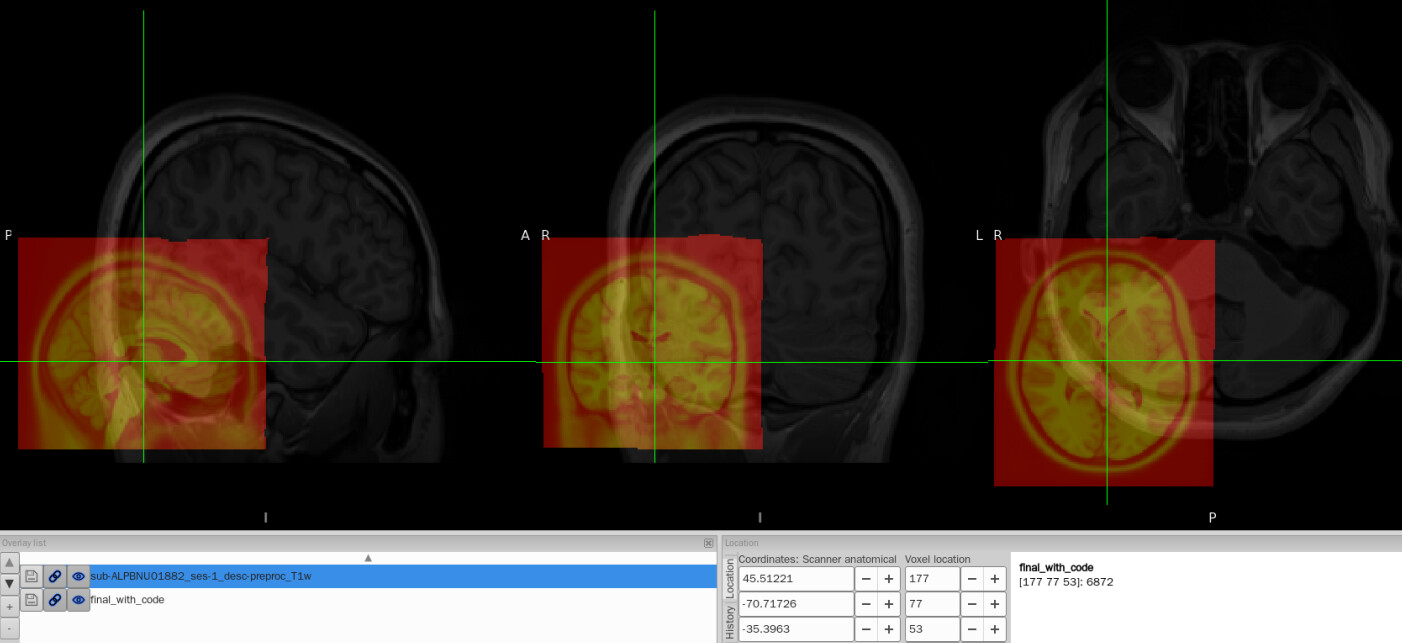

I tried to convert the ANTs-format warp (from-MNI152NLin2009cAsym_to-T1w_mode-image_xfm.h5) generated by fMRIPrep into FSL format (from-MNI152NLin2009cAsym_to-T1w_mode-image_xfm_fsl.nii.gz) using c3d affine tool, so that I could use it later in pyAFQ for tractography. The conversion itself works fine, but once I add intent code to FSL xfm header(intent code 2006), the warp seems to be damaged. To be specific, the FSL warp applied to MNI template shifted to the lower-left corner and it no longer aligns with the T1w image.